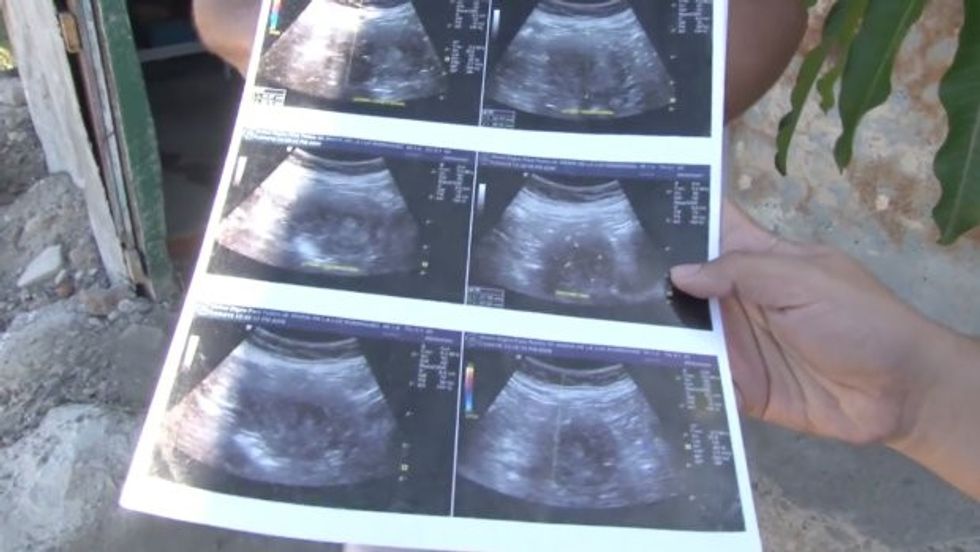

2000:"Pic shows: Maria de la Luz's ultrasound images This is the 70-year-old woman reportedly six months pregnant with her eighth child and she will apparently become the oldest new mother in history if she gives birth. The mum-to-be identified as Maria de la Luz, lives in Mazatlan, a city in the Mexican state of Sinaloa, and if the baby girl is born it will make her four years older than the current record holder. Maria del Carmen Bousada de Lara is the oldest verified mother in the world. She was aged 66 years and 358 days when she gave birth to twin baby boys, Christian and Pau, in December 2006. They were delivered prematurely by caesarean section and weighed 3.5 lbs (1.6 kilogrammes) each. Maria de la Luz who is now set to become the world's oldest mother has shown the media ultrasound scans which she says confirm she is six months pregnant with a baby girl. She said: "They told me it is a girl. Look, you can see her little face." The woman, who did not reveal any details of the pregnancy including whether she had had IVF treatment or similar, says she first suspected she was pregnant three months ago. She told reporters: "My legs hurt and I was vomiting and felt dizzy. Now they have done around 10 ultrasounds in a private clinic and in the (public) social security hospital. The doctors could not believe it." Omkari Panwar from the Indian state of Uttar Pradesh, gave birth to twins in 2008 but her claim to have been 70 was not provable. Likewise there were also other women that were older when they had children and claimed to be of a similar age but again none of the ages have been verified. Maria told reporters that some of her children were not happy with the news that she was pregnant, saying they told her she was too old for "those things". She has an appointment with a gynaecologist on 18th July and she says she is expecting to have a caesarean-delivery because of her age. Bousada de Lara admitted that she had lied to physicians about her age when seek 16:"CEN/La Republica